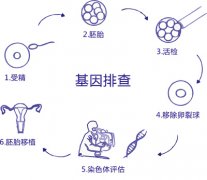

性别筛选(Sex Selection) 性别筛...